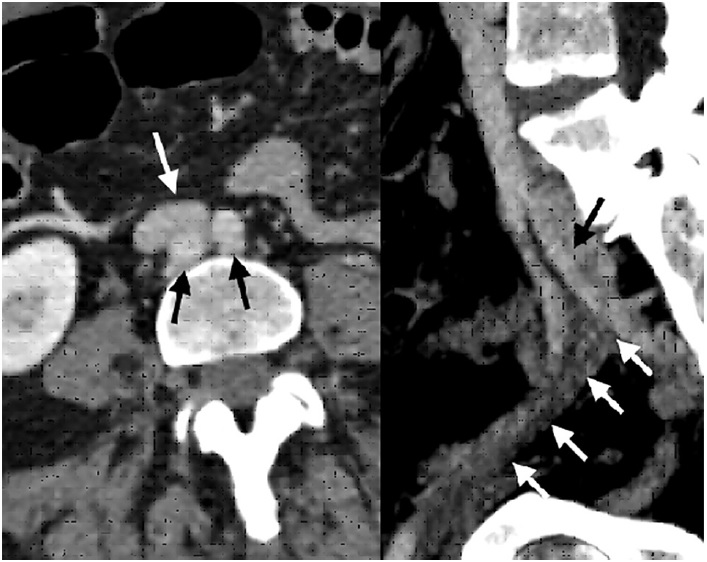

A las 24 horas del alta presenta registro febril, regular estado general, acompañado de lengua aframbuesada, edema bipalpebral y conjuntivitis. Se interna. Por laboratorio se constatan parámetros de inflamación, IgG para SARS-CoV 2 positivo y al repetir ecocardiograma Doppler (Figura 1) presenta dilatación aneurismática de ambas coronarias con función ventricular conservada (Tabla 1, se detallan los valores de las coronarias con sus respectivos Z score, en los sucesivos controles ecocardiográficos). Se reasume el cuadro como SIM-C. Recibe tratamiento inmunomediado y antiagregante plaquetario con gammaglobulina (2 gr/kg/dosis), metilprednisolona (10 mg/kg/dosis, 3 pulsos), AAS 5 mg/kg/día. Presenta leve mejoría clínica y analítica. El control cardiológico a los 5 días revela similares características. Se lo clasifica como resistente al tratamiento y se indica Infliximab (5 mg/kg). Evoluciona favorablemente, con marcada mejoría clínica y cardiovascular; se otorga el alta luego de 16 días. Se programa control cardiológico y reumatológico más tratamiento antiagregante y antiinflamatorio.

Fig. 1 Ecocardiograma Doppler 2D (eje corto de los vasos): se observa coronaria derecha en la parte superior, y coronaria izquierda en la inferior.